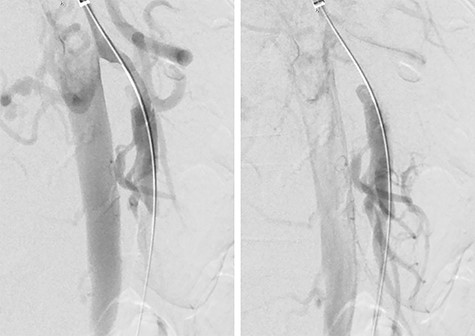

She was admitted and maintained on bowel rest and heparin infusion. Given persistent pain after 2 days of non-operative management, an abdominal arteriogram was performed through a left axillary artery cutdown. The dissection was identified 1.5 cm distal to the origin of the SMA (Fig. 2). Intravascular ultrasound was used to determine diameters and landing zones for stent placement (Fig. 3). The dissection was initially treated with a 6 mm × 40 mm self-expanding stent followed by post-dilation with 4 mm × 40 mm and 6 mm × 40 mm balloons. A 5 mm × 19 mm stent graft was deployed proximally with small overlap and ~3-mm extension into the aorta. Completion angiogram showed <10% residual stenosis (Fig. 4). As the right external iliac artery dissection was small and asymptomatic, no intervention was performed.

Intravascular ultrasound probe within the true lumen, with false lumen visualized to the bottom right of the probe.